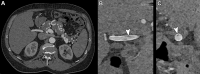

CT systems equipped with photon-counting detectors (PCDs), referred to as photon-counting CT (PCCT), are beginning to change imaging in several subspecialties, such as cardiac, vascular, thoracic, and musculoskeletal radiology. Evidence has been building in the literature underpinning the many advantages of PCCT for different clinical applications. These benefits derive from the distinct features of PCDs, which are made of semiconductor materials capable of converting photons directly into electric signal. PCCT advancements include, among the most important, improved spatial resolution, noise reduction, and spectral properties. PCCT spatial resolution on the order of 0.25 mm allows for the improved visualization of small structures (eg, small vessels, arterial walls, distal bronchi, and bone trabeculations) and their pathologies, as well as the identification of previously undetectable anomalies. In addition, blooming artifacts from calcifications, stents, and other dense structures are reduced. The benefits of the spectral capabilities of PCCT are broad and include reducing radiation and contrast material dose for patients. In addition, multiple types of information can be extracted from a single data set (ie, multiparametric imaging), including quantitative data often regarded as surrogates of functional information (eg, lung perfusion). PCCT also allows for a novel type of CT imaging, K-edge imaging. This technique, combined with new contrast materials specifically designed for this modality, opens the door to new applications for imaging in the future.